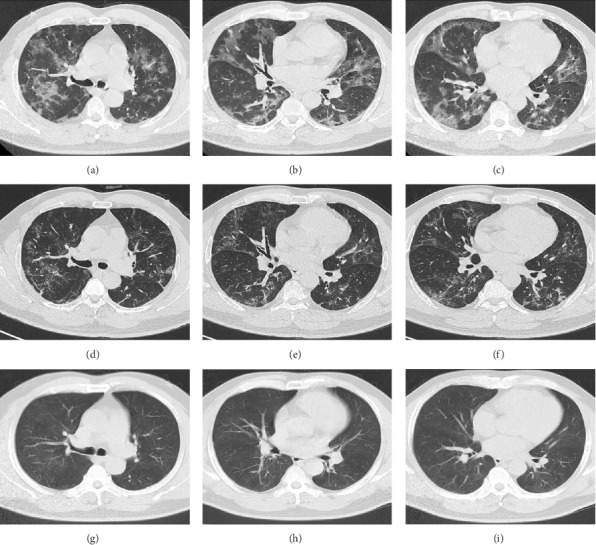

The concurrence of COVID-19 and tracheobronchial aspergillosis (TBA) is rarely documented in clinical practice. This report presents a case of TBA in a patient diagnosed with COVID-19 prior to the administration of immunosuppressive agents. This case underscores the necessity of considering fungal infections in patients with COVID-19, even during the early stages of the disease. The combination of timely bronchoscopy, antiviral therapy, and antifungal treatment resulted in favorable therapeutic outcomes for the patient.